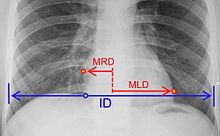

Cardiothoracic ratio =

where:[23]

MRD = greatest perpendicular diameter from midline to right heart border

MLD = greatest perpendicular diameter from midline to left heart border

ID = internal diameter of chest at level of right hemidiaphragm

• Chest X-Ray: X-ray images help see the condition of the lungs and heart. If the heart is enlarged on an X-ray, other tests will usually be needed to find the cause. A useful measurement on X-ray is the cardio-thoracic ratio, which is the transverse diameter of the heart, compared with that of the thoracic cage."[24] These diameters are taken from PA chest x-rays using the widest point of the chest and measuring as far as the lung pleura, not the lateral skin margins. If the cardiac thoracic ratio is greater than 50%, pathology is suspected, assuming the x-ray has been taken correctly.[25] The measurement was first proposed in 1919 to screen military recruits. A newer approach to using these x-rays for evaluating heart health takes the ratio of heart area to chest area and has been called the two-dimensional cardiothoracic ratio.[26]